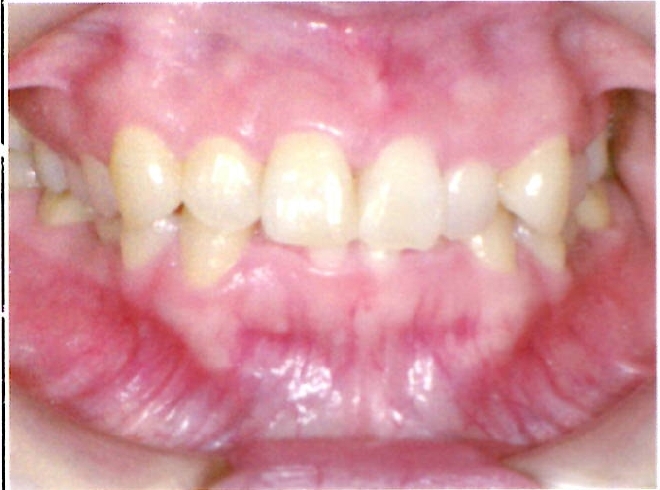

| 主訴・治療前の状態 | 前歯が噛み合っていない状態(開咬傾向)で、犬歯がやや前方に突出しており、見た目にお悩みがありました。 |

| 治療内容 | 上下左右の第一小臼歯(4番)計4本を抜歯し、そのスペースを利用して歯列を整え、前歯の噛み合わせを改善しました。 |

| 治療結果 | 前歯がしっかり噛み合うようになり、見た目も美しく整いました。患者様の満足度が非常に高かった症例です。 |